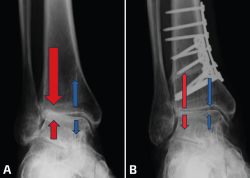

Cualquier alteración de la transmisión de cargas de la extremidad inferior puede producir una sobrecarga mecánica anormal y mantenida en el tobillo que puede llevar a una artrosis asimétrica. Cuando la transmisión de cargas se concentra en el área lateral del tobillo (región cóncava de la deformidad) se producirá un desgaste asimétrico de esa zona del tobillo (Figura 2).

Figura 2. A: alteración de cargas pre-osteotomía; B: osteotomía supramaleolar de cierre medial.

En los casos de malalineamiento en valgo, la OTT-SM debe lograr un efecto varizante. Esto se puede lograr con diferentes modelos de OTT; la más comúnmente utilizada es la OTT en cuña de cierre medial, que se realiza mediante un abordaje medial en la tibia distal, asociado o no a OTT de apertura en peroné (Figura 2).